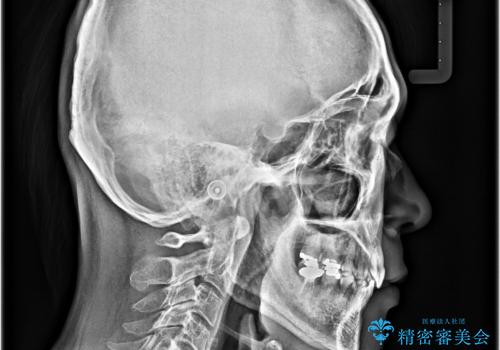

- 口元の突出感を気にして来院された患者様です。

強い咬合力と上顎前歯の傾斜により前歯が突出し、唇が閉じにくい状況であったため、上下左右の第一小臼歯4本を抜歯し、ワイヤー装置にて矯正治療を行うこととしました。

非常に咬合力が強いため、抜歯したスペースが閉じるのか不安でしたが、順調に歯が移動し、予定よりも早く治療を終えることができました。